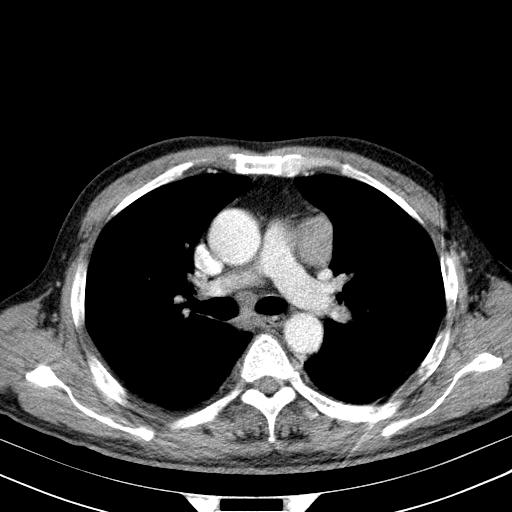

还见胃窦壁增厚!转移亦有可能!

大家看看肝脏右叶片状低密度影是什么改变啊?

淋巴瘤?肝脏请增强后说啊

多发肿大淋巴结影,肝内改变需结合强化观察